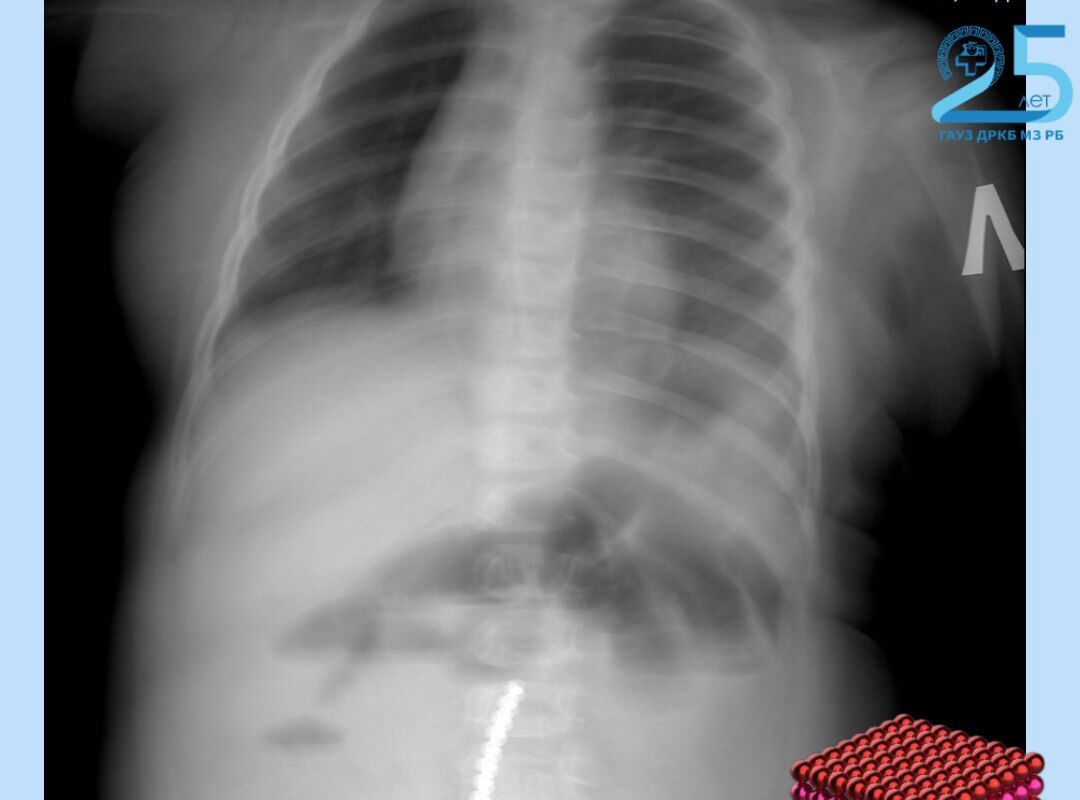

Маленький пациент поступил в больницу с приступами рвоты в тяжелом состоянии. Рентген показал множество инородных тел в желудочно-кишечном тракте. Выяснилось, что несовершеннолетний наглотался магнитных шариков от игрушки.

«Нам удалось удалить девять магнитов эндоскопически (ФГДС). Однако остальные мигрировали по кишечнику, вызвав перфорацию. Петли тонкой, сигмовидной и слепой кишки слиплись между собой из-за магнитного притяжения», — рассказал хирург-эндоскопист ДРКБ Булат Шагдаров.

Хирурги провели открытую операцию, из-за притянувшихся друг к другу магнитов им пришлось удалить поврежденный участок тонкой кишки. Врачи также ушили свищи и извлекли аппендикс, куда опустилась часть магнитов. Сейчас ребенок переведен из реанимации в обычное отделение, его состояние оценивается как стабильное.